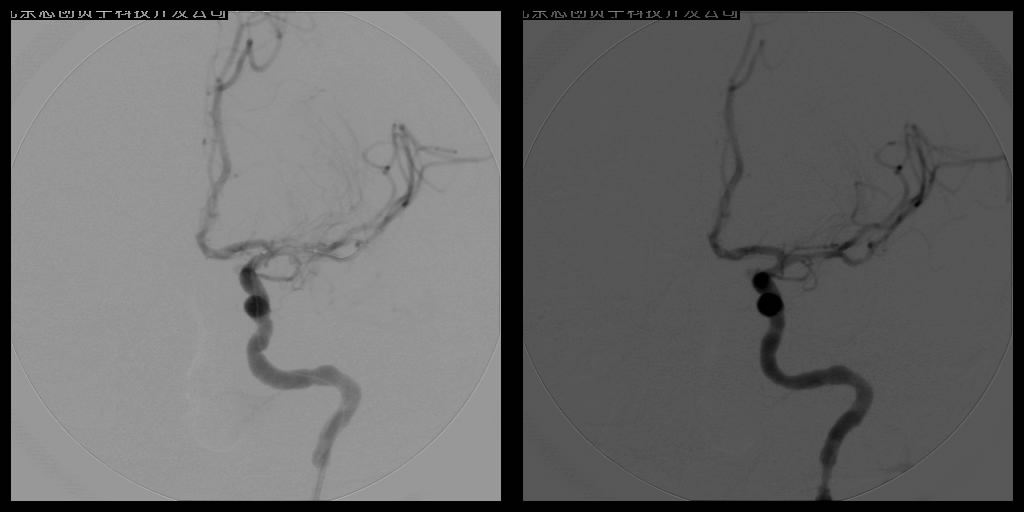

血管內(nèi)溶栓及機械取栓

針對頸動脈和椎基底動脈狹窄等缺血性腦血管病的防治,血管球囊擴張成形術(shù)和血管內(nèi)支架植入成形術(shù)已經(jīng)成為治療頸動脈狹窄及椎基底動脈狹窄十分重要的手段,所用支架可分為球囊擴張式支架和自膨式支架。

支架植入